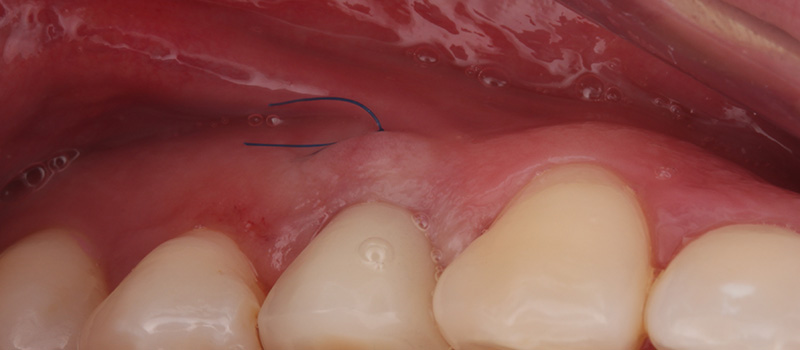

Fig. 07 : radiographie rétro-alvéolaire de contrôle après 4 mois de cicatrisation.

Fig. 08 : gestion des tissus mous péri-implantaires.